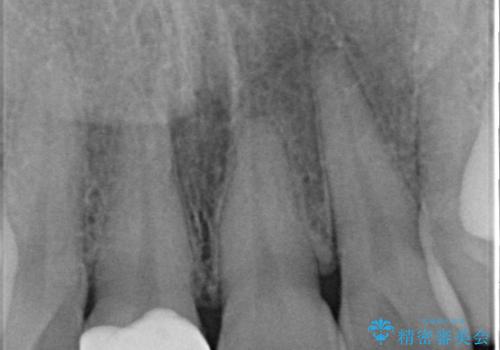

また、右上の前歯は裏側までヒビが入っていることや、1層構造のラミネートよりも2層構造のオールセラミッククラウンの方が色の再現性も高いことから、右上前歯1本のクラウン治療をおすすめしました。

今回は、歯肉炎があるため、その治療を行ってからクラウンを製作しました。

歯肉炎がない場合は、1か月ほどで治療が完了します。逆に、炎症がひどい場合は、治療期間が長くなります。